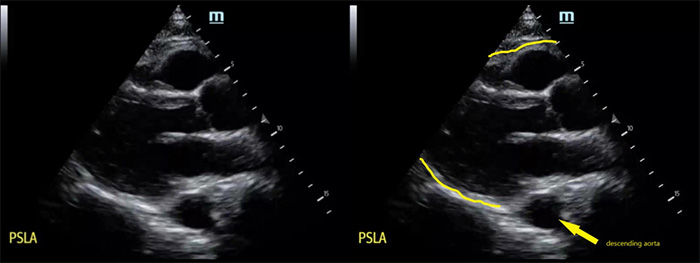

- The descending aorta is the imaging landmark to help determine if free fluid is in the pericardial space or the pleural space when using the parasternal approach (Figure 11).

Figure 11. Parasternal long axis (PSLA) view of the heart without pericardial effusion, note descending aorta in the far field